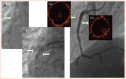

Patients with calcified, fibrotic native coronary vessels with prior suboptimal stenting outcomes are at major risk of stent thrombosis and could face serious consequences if untreated. In cases of multiple layers of under-expanded stents, the risk is multiplied. If conventional balloon post-dilatation is unsuccessful after stent implantation without proper lesion preparation, few interventional options remain. The authors report on a patient with prior numerous right coronary unsuccessful coronary interventions resulting in partially crushed multiple layers of stent material with critical lumen narrowing caused by stent under-expansion. Balloon angioplasty and stent rotational atherectomy (ROTA) had been attempted to overcome stent under-expansion but were unsuccessful. The authors investigated a new combination therapy of laser atherectomy (ELCA) and super high-pressure balloon (OPN non-compliant balloon) to treat single or multiple layers of stent with severe under-expansion due to fibrotic, calcified tissue surrounding the under-expanded stent structure.